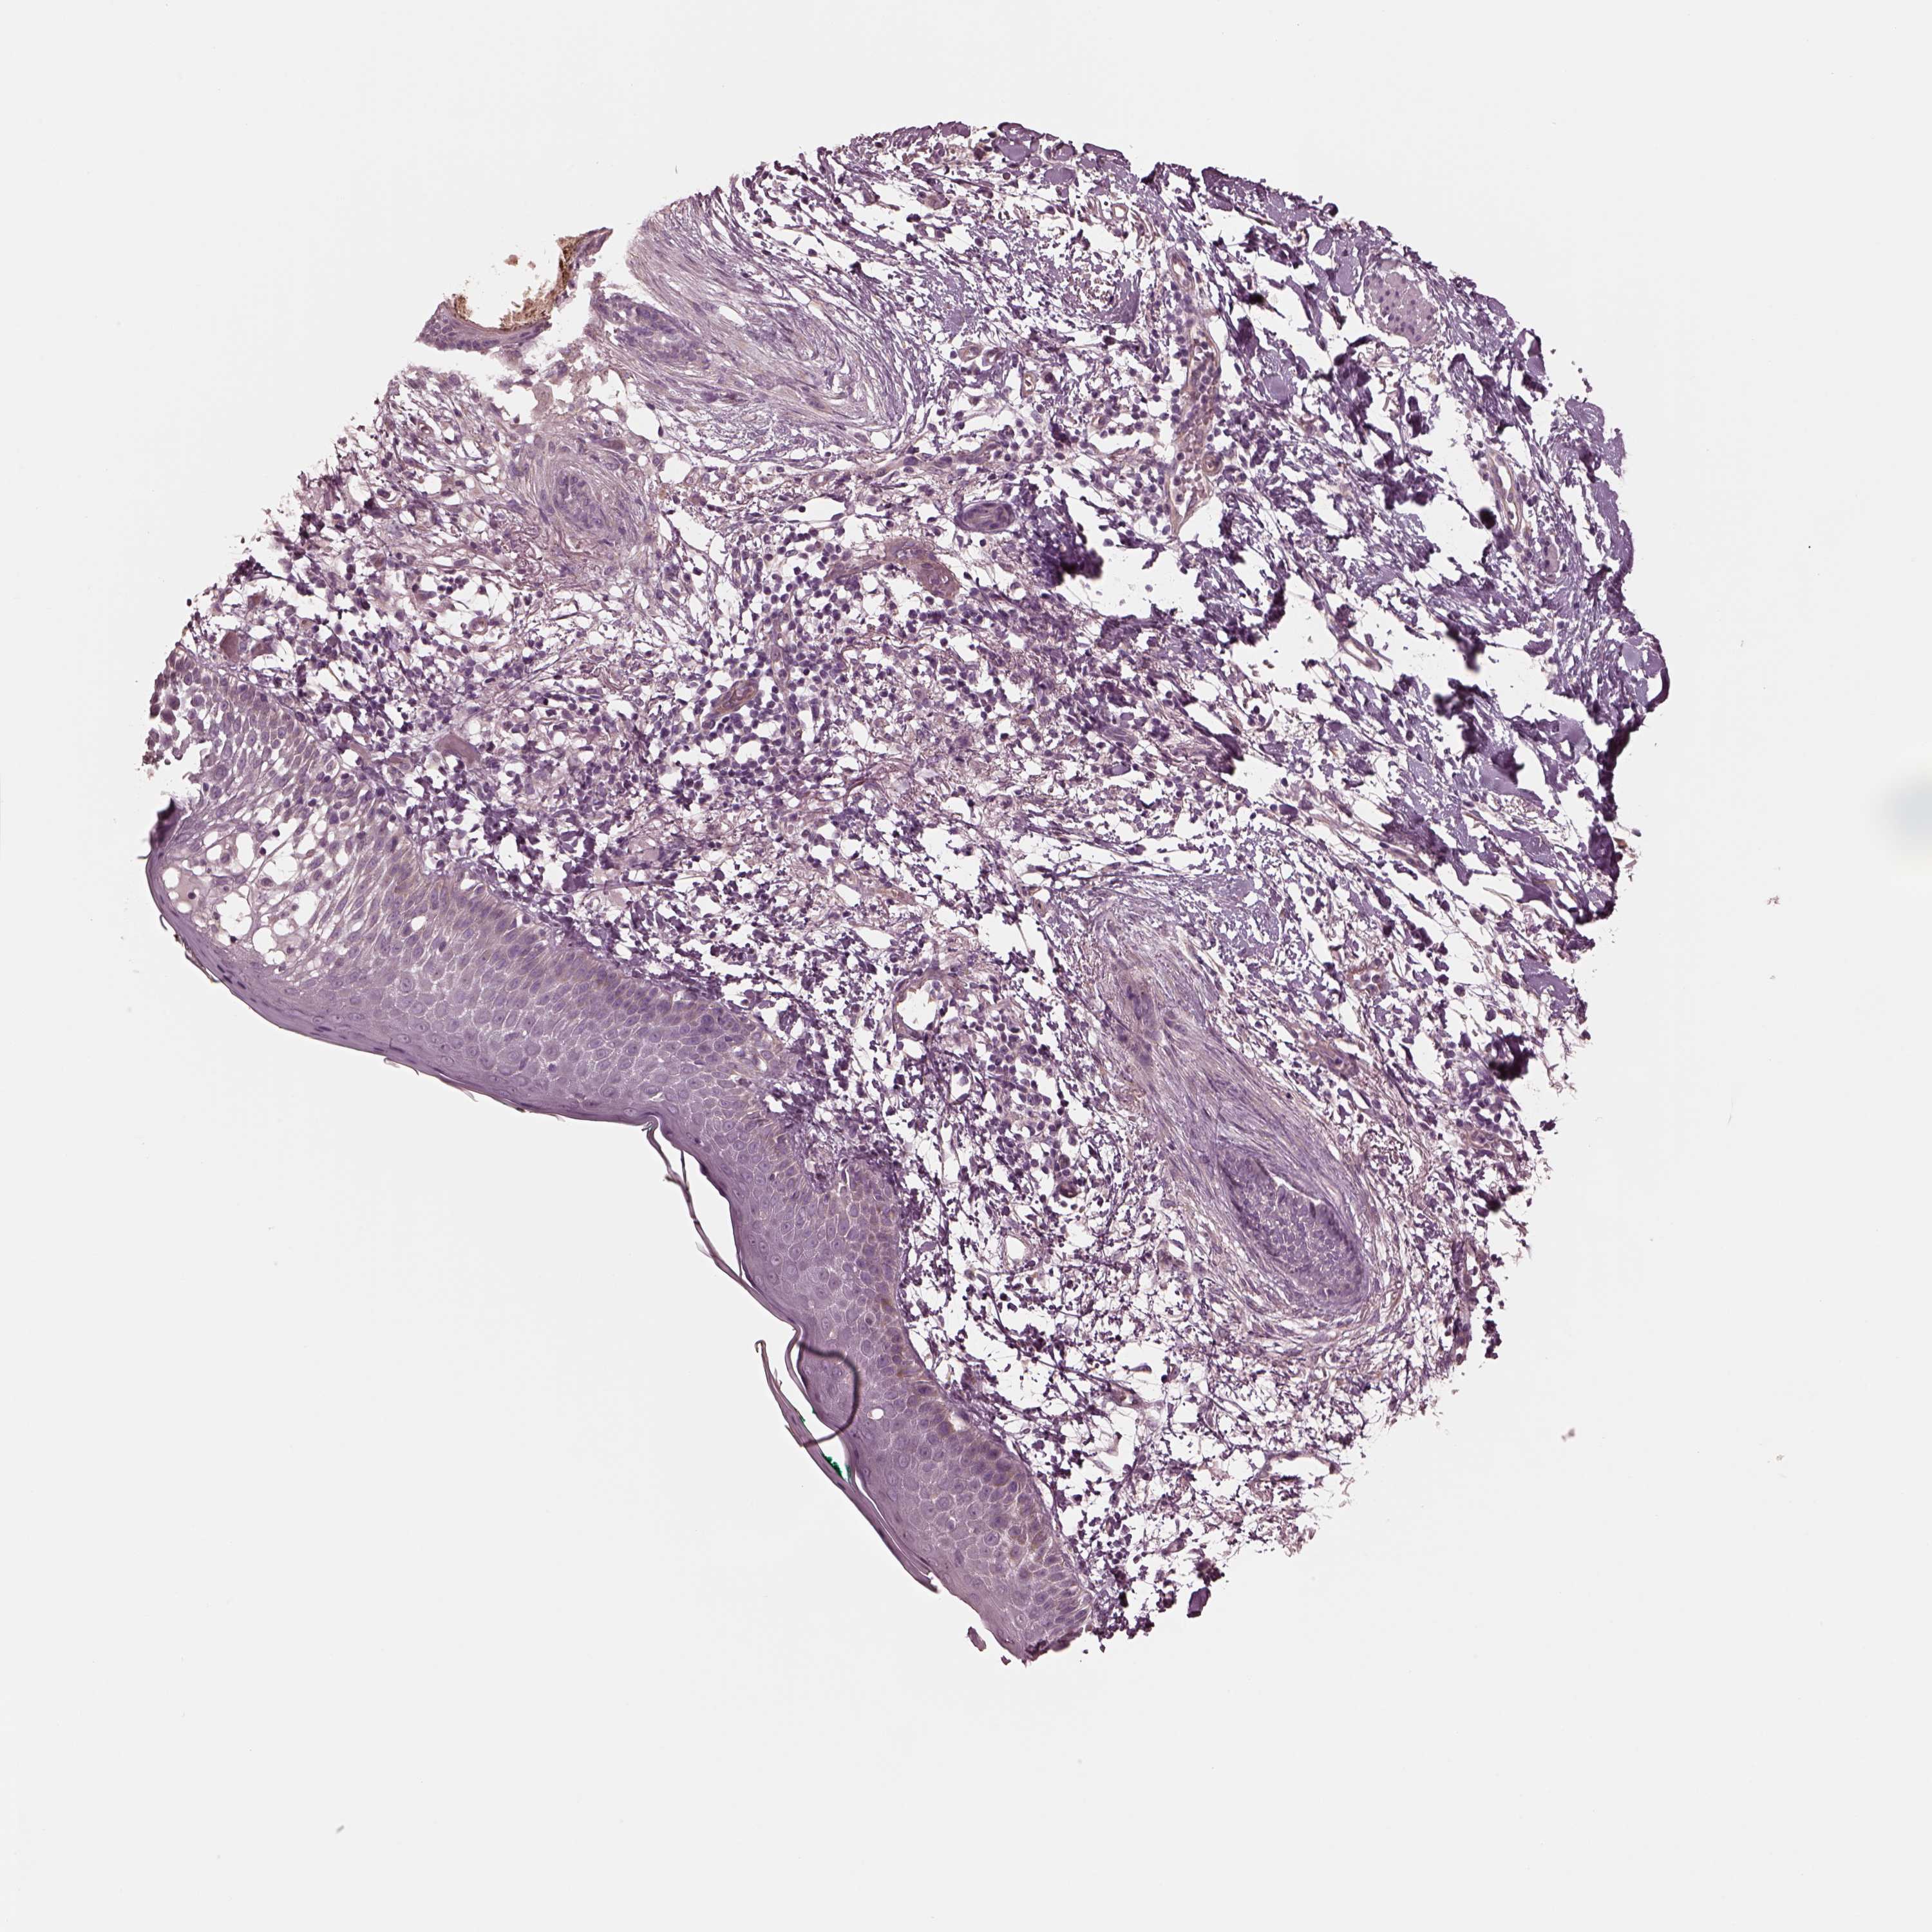

CANCER SKIN CANCER Show tissue menu

Basal cell and squamous cell cancer

SKIN CANCER - Protein expressioni

A mouse-over function shows sample information and annotation data. Click on an image to view it in a full screen mode. Samples can be filtered based on level of antibody staining by selecting one or several of the following categories: high, medium, low and not detected. The assay and annotation is described here.

Each image is clickable and will lead to virtual microscopy that enables deeper exploration of all samples and also displays staining intensity scores, fraction scores and subcellular localization as well as patient and tissue information for each sample.

Antibody HPA038811

Staining

High

Medium

Low

Not detected

Intensity

Strong

Moderate

Weak

Negative

Quantity

>75%

75%-25%

<25%

None

Location

Nuclear

Cytoplasmic/membranous

Cytoplasmic/membranous,nuclear

Basal cell carcinoma

Squamous cell carcinoma, NOS